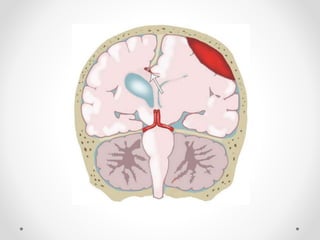

Drawing shows a lateral DTH with compression of the posterior cerebral

artery (white arrowhead) and third cranial nerve (black arrowhead). Note

the ipsilateral blown pupil (arrow) and contralateral temporal horn

dilatation (*)